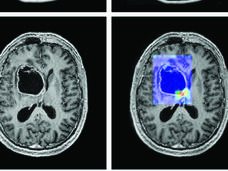

Can Artificial Intelligence Help See Cancer in New, and Better, Ways?

Researchers have been developing artificial intelligence (AI) tools that could make cancer imaging faster, more accurate, and more informative. But there are also questions about whether these tools are ready for doctors’ offices, whether they will actually help people, and whether that benefit will reach all—or only some—patients.